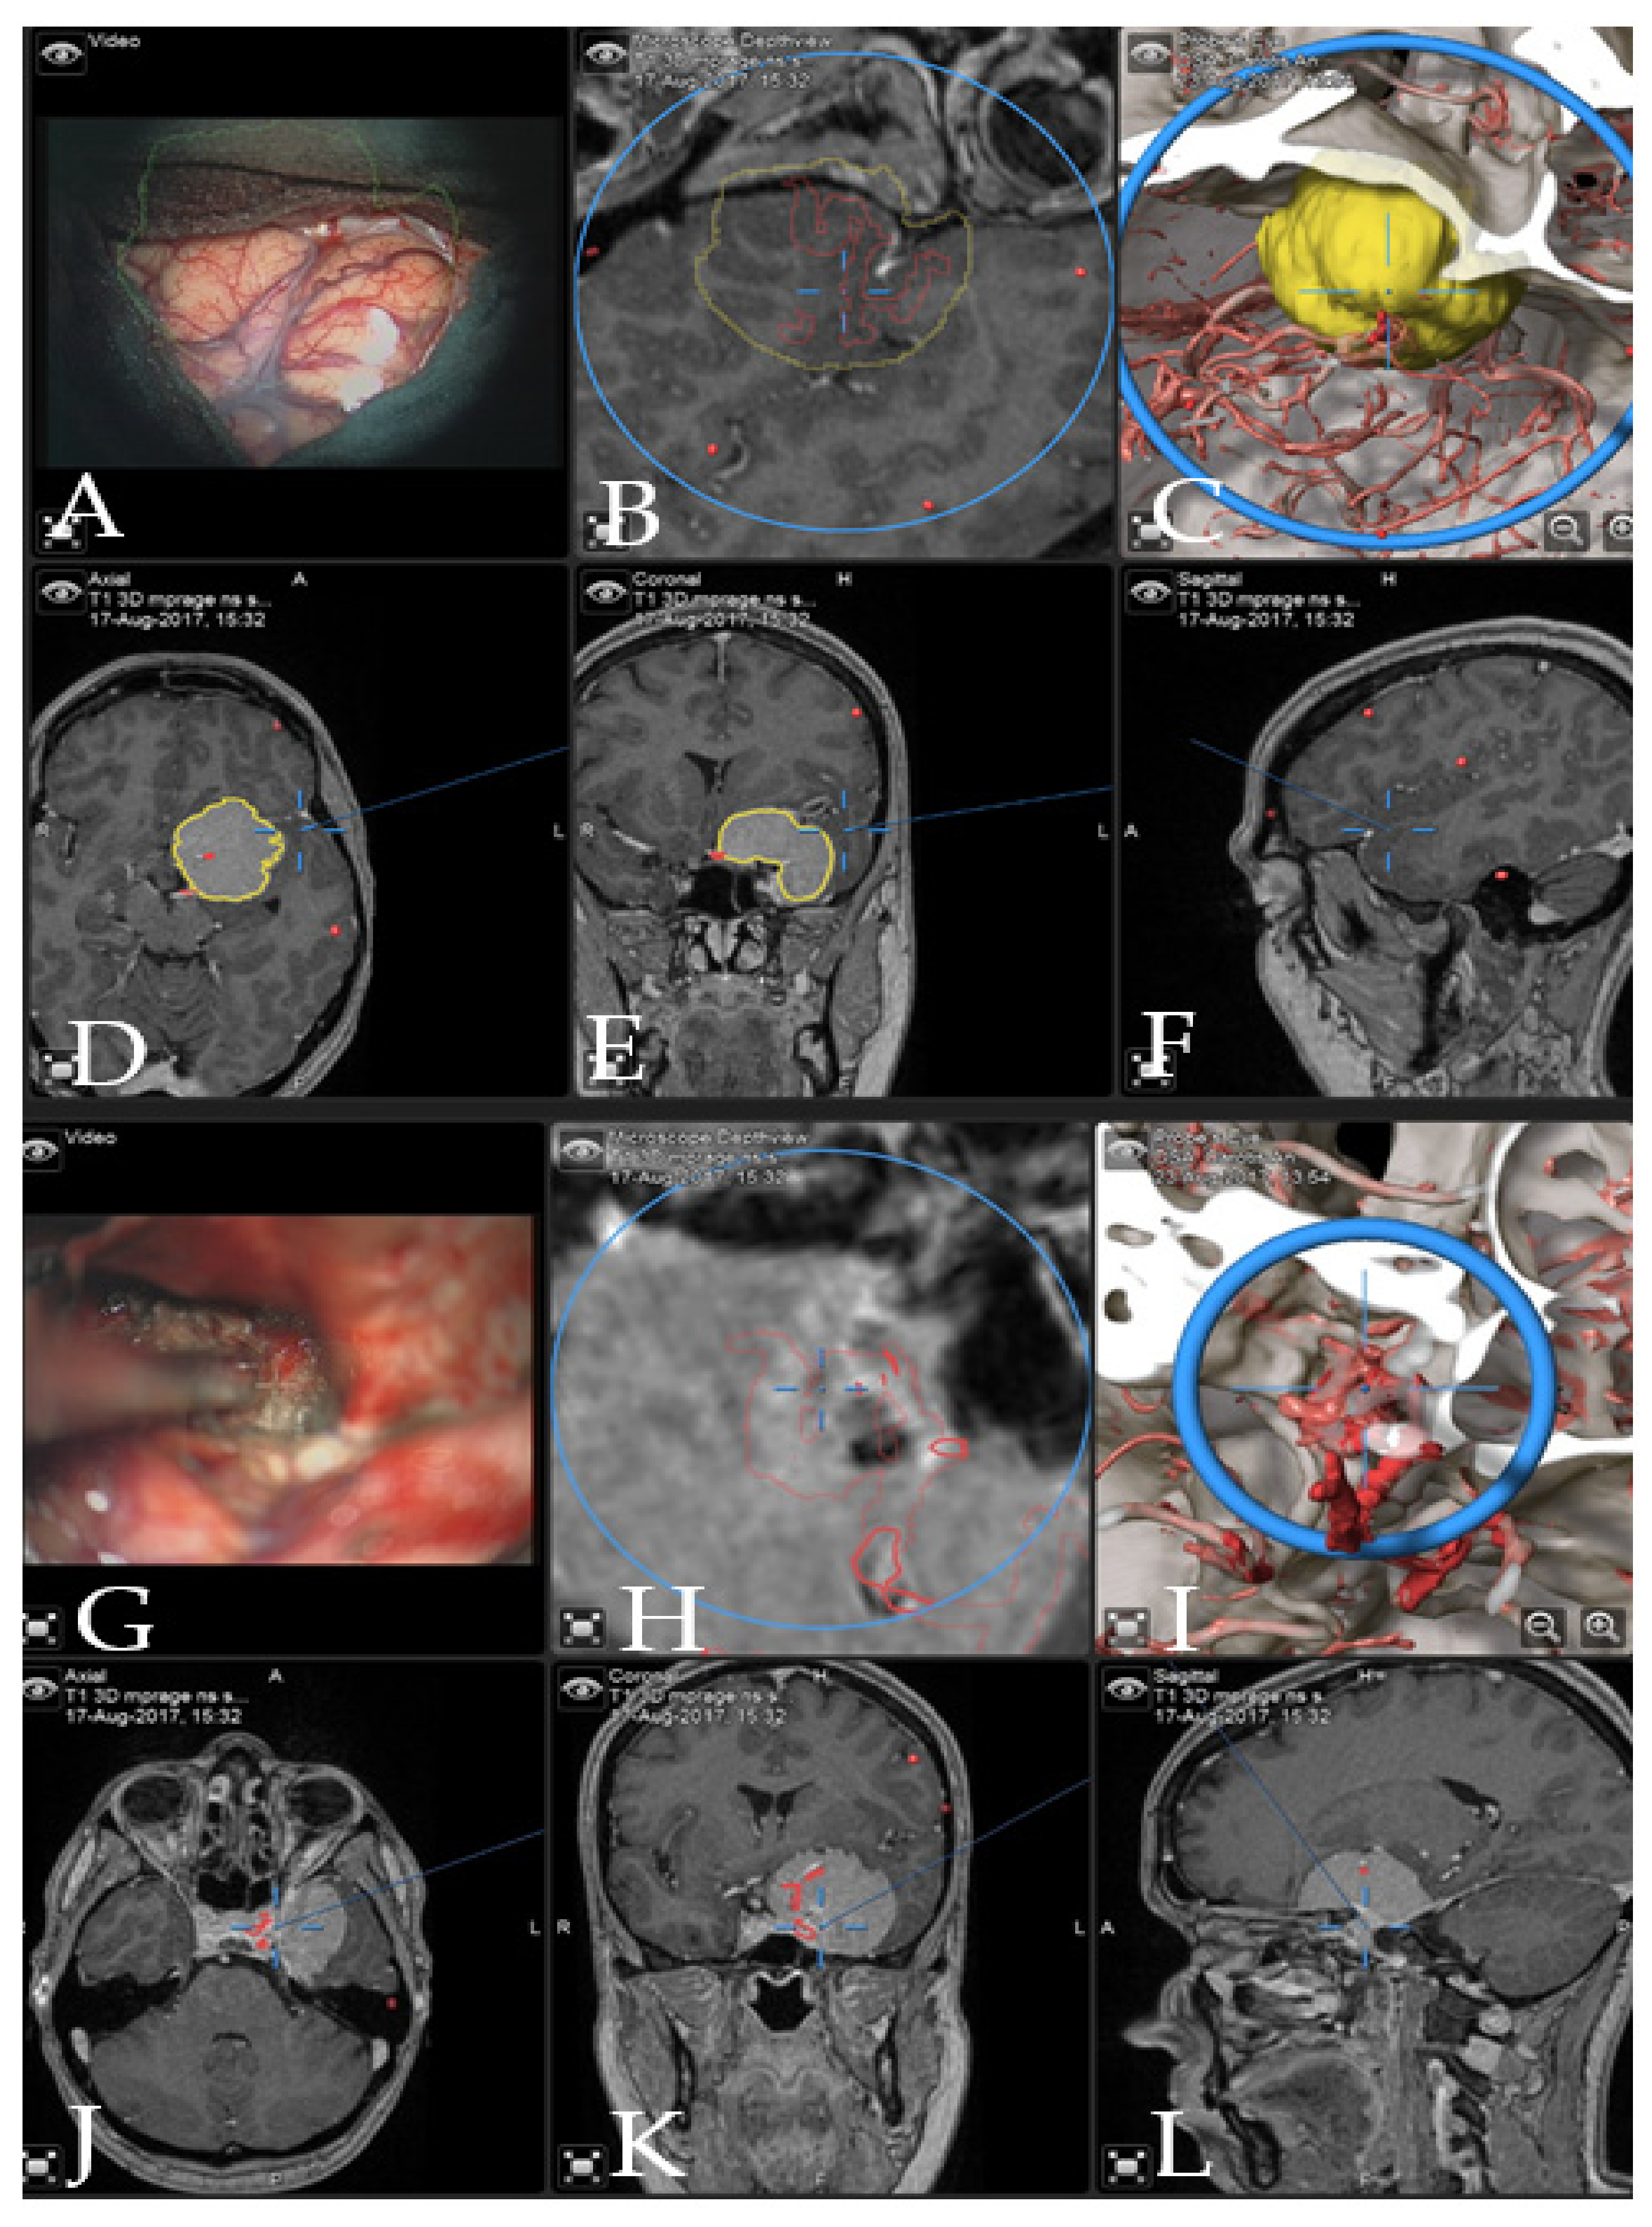

Illustrative Cases